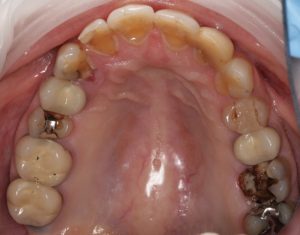

At Southington Dentistry we offer various types of dental implants to suit your dental needs. These implants include full upper and lower, anterior, posterior, and single-tooth replacement options:

Full Upper or Lower Tooth Replacements

This process involves replacing all of the the upper or lower set of teeth and can be removable and clip in or fixed permanently in certain cases.